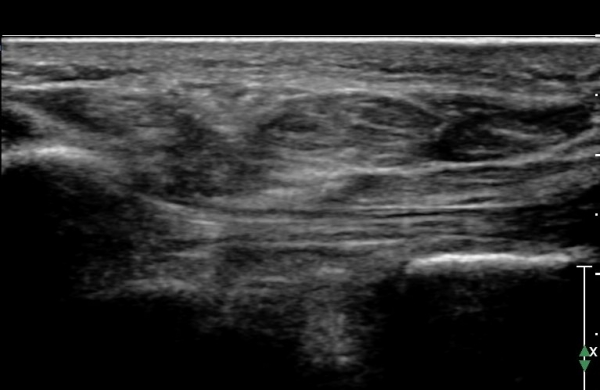

ÃÊÀ½ÆÄ°Ë»ç :  Àü°ÅºñÀδë Á¾´Ü¸é°Ë»ç¿¡¼­ Àü°ÅºñÀδëÀÇ Àú¿¡ÄÚ À§ÃàÀÌ °üÂûµÇ°í °Å°ñ °æºÎÀÇ °ß¿­°ñÀý ¹×

°Å°ñÁÖ»ó°ñ°üÀý ºÎÁ¾ÀÌ °üÂûµÈ´Ù(»çÁø 1).